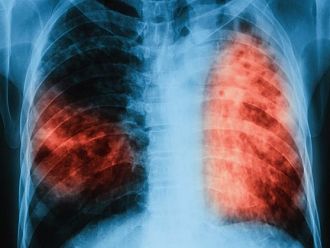

„Прегледите и изследванията са напълно безплатни, включително и за неосигурените лица. На всеки, който реши да провери своето състояние, ще бъде извършен преглед и ще се назначи проба манту, а при необходимост и допълнителни изследвания – рентгенова снимка и изследване на материал за туберкулозни бактерии. Подобни кампании позволяват своевременно предприемане на мерки за хоспитализация, лечение и прекъсване на веригата за предаване на инфекцията”, коментира д-р Лазарова.

При последната кампания, проведена през март т.г. са прегледани 106 човека, като 89 от тях са дали положителни отговори на два и повече въпроси от анкетата. Направени са 81 проби манту, 34 рентгенографии на бял дроб и 14 микробиологични изследвания. Няма открити случаи на туберкулоза. При 10 лица е установен повишен риск от заболяване. На тях е назначена химиопрофилактика с предпазна цел.